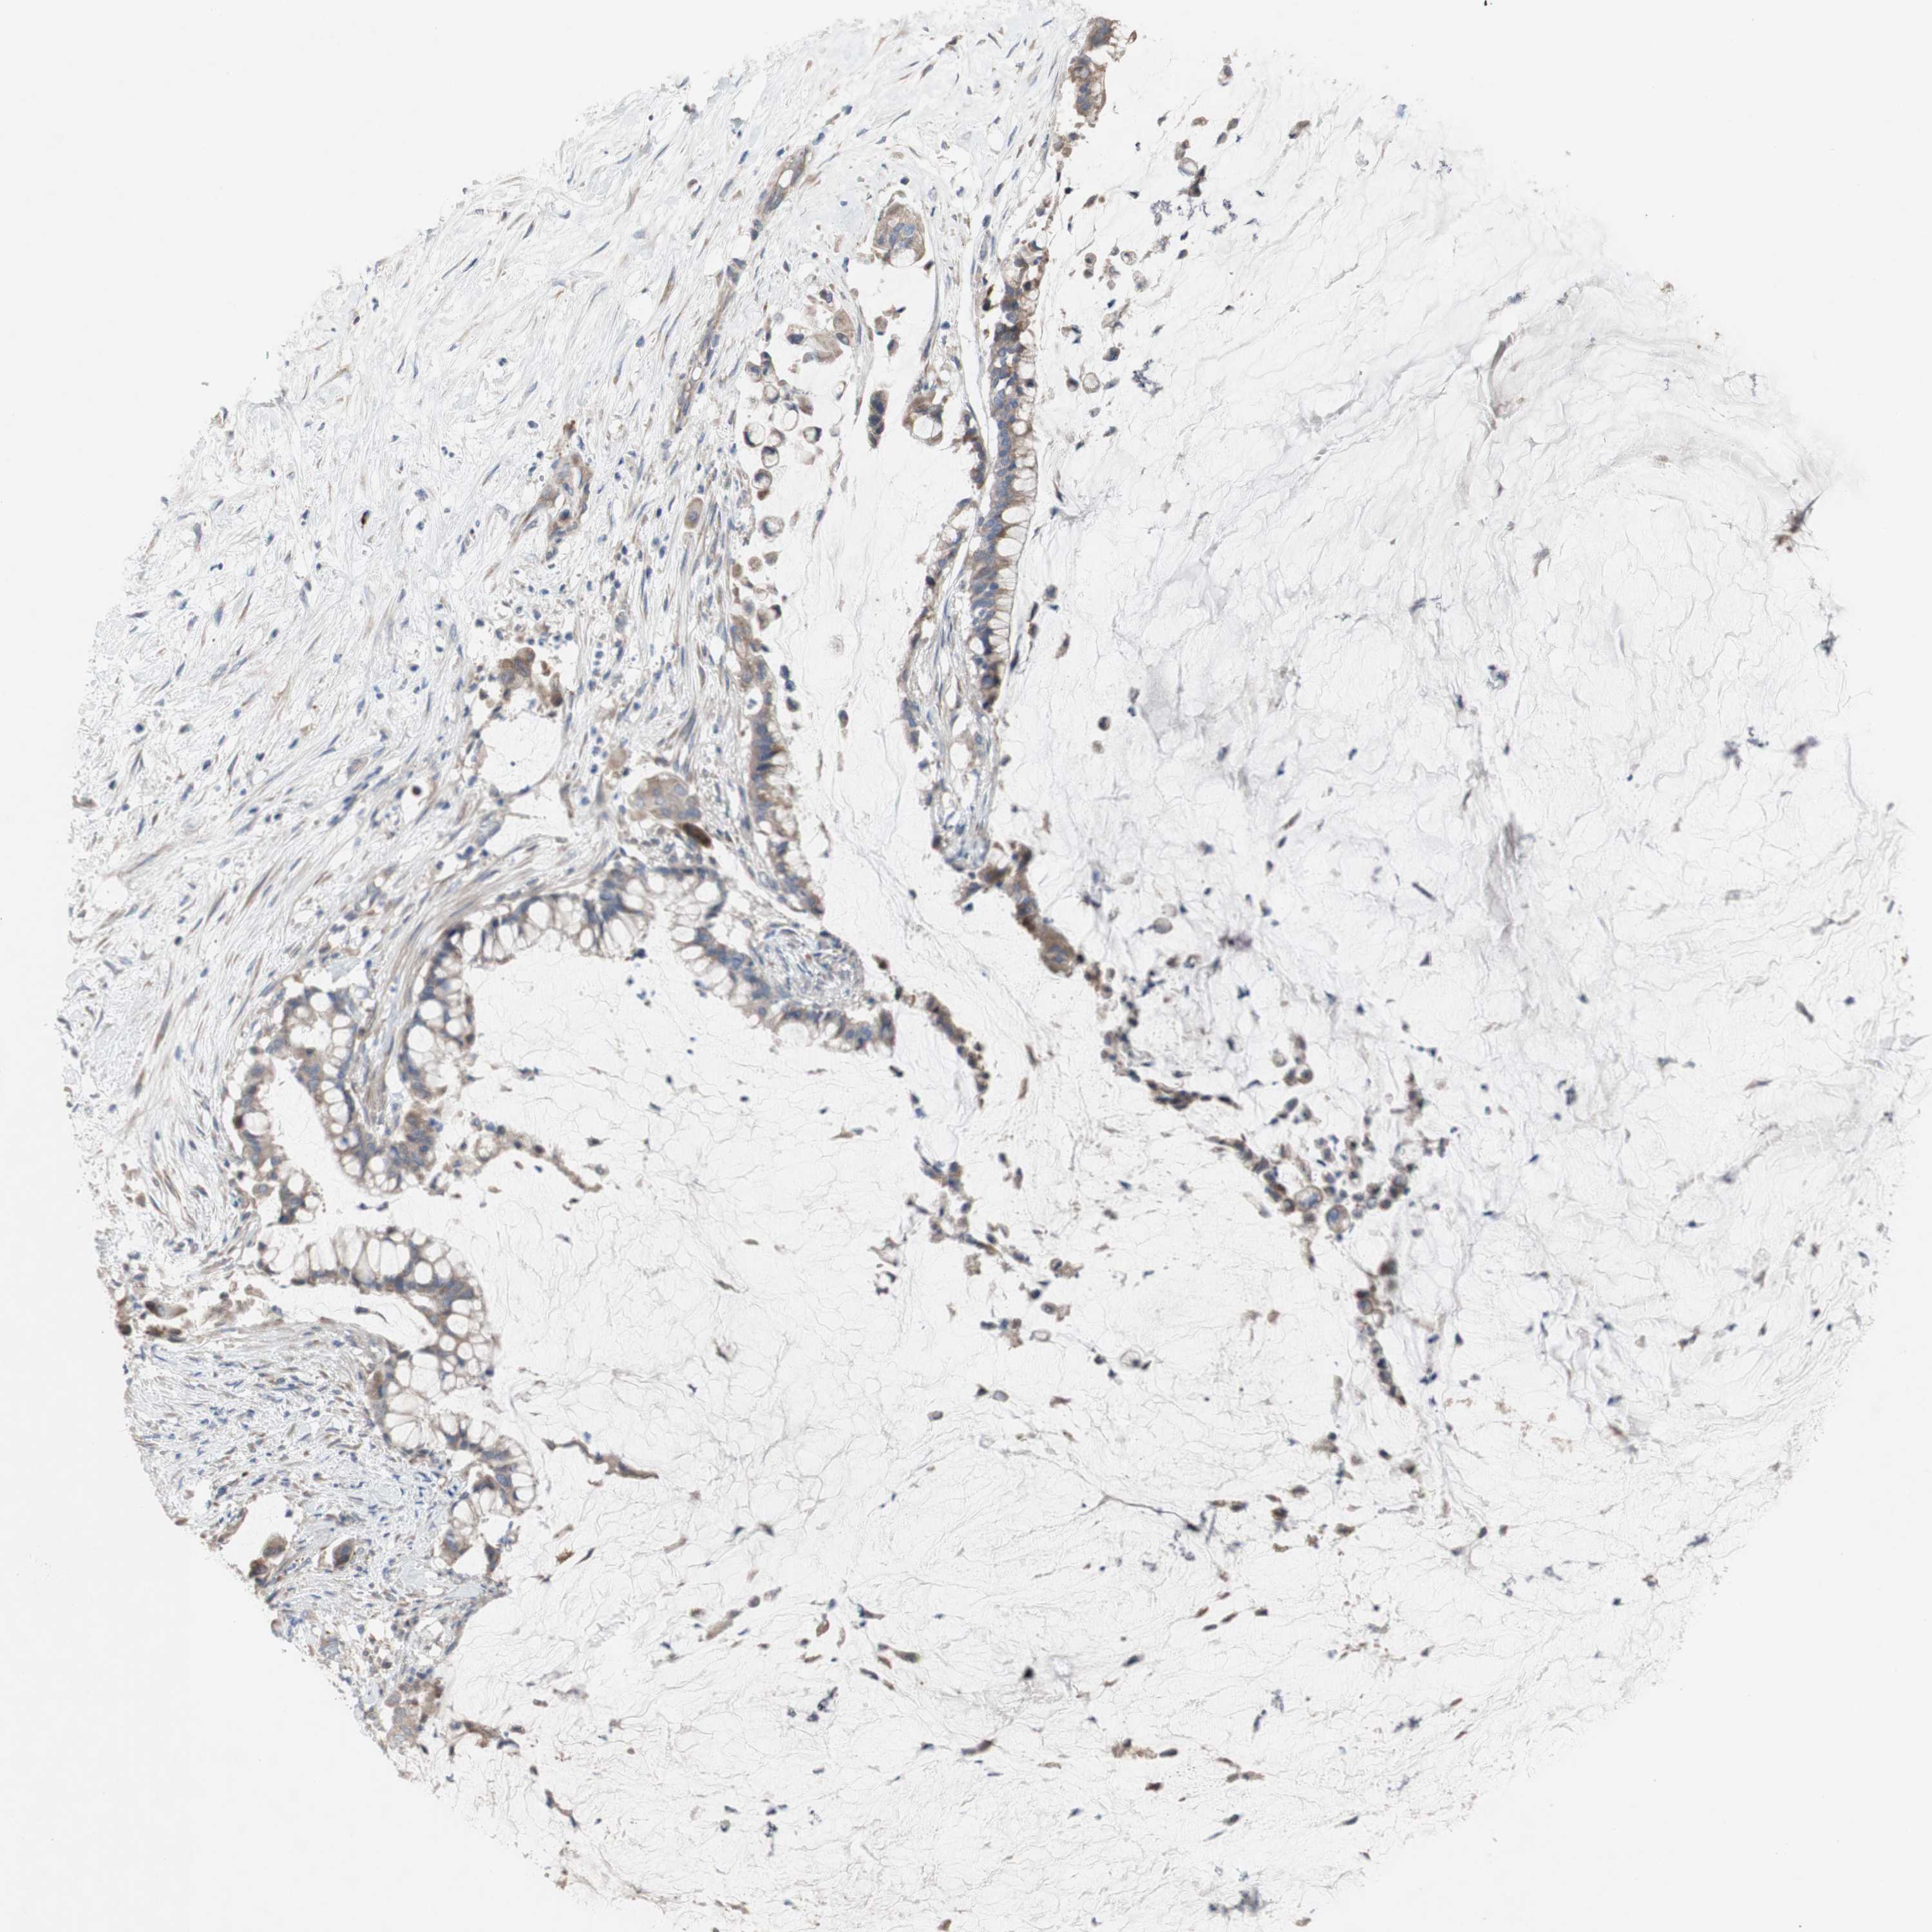

PANCREATIC CANCER - Protein expressioni

A mouse-over function shows sample information and annotation data. Click on an image to view it in a full screen mode. Samples can be filtered based on level of antibody staining by selecting one or several of the following categories: high, medium, low and not detected. The assay and annotation is described here.

Note that samples used for immunohistochemistry by the Human Protein Atlas do not correspond to samples in the TCGA dataset.

Antibody stainingi

Antibody staining in the annotated cell types in the current human tissue is reported as not detected, low, medium, or high, based on conventional immunohistochemistry profiling in selected tissues. This score is based on the combination of the staining intensity and fraction of stained cells.

Each image is clickable and will lead to virtual microscopy that enables deeper exploration of all samples and also displays staining intensity scores, fraction scores and subcellular localization as well as patient and tissue information for each sample.

Antibody HPA009295

Staining

High

Medium

Low

Not detected

Intensity

Strong

Moderate

Weak

Negative

Quantity

>75%

75%-25%

<25%

None

Location

Nuclear

Cytoplasmic/membranous

Cytoplasmic/membranous,nuclear

Adenocarcinoma, NOS